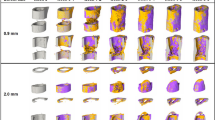

Impedance distinguishes fractures vs. critical-sized defects

To measure impedance of a changing fracture callus over the course of healing, we implanted commercially-fabricated sensors into broken tibias stabilized in an external fixator model (Fig. 1A) for initial validation. These 250 µm diameter FR4 (a glass-reinforced epoxy laminate material) sensor pins (Fig. 1B–D) were placed into either 0.5 mm (N = 6) or 2 mm (N = 5) defects to determine if we could distinguish EIS trends between previously established healing versus non-healing fracture models, respectively42,43,44. Measurements were taken twice weekly from 20 Hz to 1 MHz with mice sacrificed at scattered time points up to day 28. Mice with 0.5 mm defects initiated a healing response with fracture calli containing a heterogeneous mixture of cartilage and new trabecular bone 14 days post-injury (Fig. 2A). However, mice with 2 mm defects contained primarily undifferentiated fibrous tissue indicating minimal healing response (Fig. 2B). Histology images have been false-colored to aid in interpretation of tissue composition (original histology images in Fig. S1A,B). Linear regression analyses indicate a significant positive relationship between electrical resistance (R) and time in mice with 0.5 mm defects (p < 0.0001), and no correlative relationship between R and time in mice with 2 mm defects (Fig. 2C). By day 28, histology for the 0.5 mm defects show new bone formation, while 2 mm critical-sized defects result in atrophic nonunions with absence of bony bridging.

Microscale sensors track changes in frequency response

A limitation of the FR4 sensor was the repeated observation of fibrous tissue around the electrodes even out to 28 days post-injury. We hypothesized this was due to the sensor’s large size relative to the defect. Consequently, we designed and built significantly smaller sensors made from 56 µm diameter platinum (Pt) wire (Fig. 1E)45. Sensors were implanted within fractures stabilized in the same external fixator model (Fig. 1F,G) with 0.5 mm defects and we again measured EIS from 20 Hz to 1 MHz twice weekly for 28 days in five mice.

In two mice, histology showed clear signs of healing, with a robust callus present between the two bone ends (Figs 2D and S1C). However, the other three mice displayed poor signs of healing, with fracture gaps dominated by an overabundance of fibrous tissue (Figs 2E and S1D). We believe the divergent healing responses were due to significant sensor movement in some fractures based on fluoroscopy images taken immediately after surgery and on day 28 before euthanasia.

The thin and flexible nature of the sensors also allowed them to be preserved throughout the histology process, enabling visualization of the specific tissue surrounding the sensor (Fig. 2F). To analyze EIS data alongside histological evidence of healing, electrical resistance (R) and reactance (X) were normalized as a ratio to the first time point after surgery (day 4). This accounted for the initial perturbation of surgery and variation between sensors and samples, enabling comparison between multiple mice. Based on all EIS plots, we found the largest spread between measurement days at 15 kHz, indicating the most functional frequency for detecting differences in fracture healing (Fig. 2G). This falls within the frequency range that can be identified as the beta dispersion, which is associated with the polarization of cell membranes, proteins, and other macromolecules26. At this frequency, normalized R and X increase with progression of fracture repair in the healing mice, but stall in the poor-healing mice. Figure 2H,I illustrate how normalized R and X as functions of frequency differ for healing and poor-healing mice from an early time point (day 7) to a late time point (day 28). The healing mice exhibit clear changes in their frequency response in both parameters relative to day 4, especially from 103 to 105 Hz. Comparatively, poor-healing mice show relatively flat frequency responses relative to day 4. The influence of callus formation on frequency response enables the clear differentiation between well-healing and poor-healing mice.